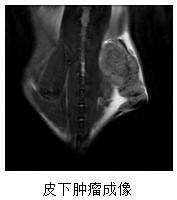

主要用途:

16A05C3391395658D85DCF901A7_89D3FFF1_7109.jpeg

E269F87F88D7F5BECEF4BDCEA8A_AD2EEFD2_7AD9.jpeg

FEE49F9EC9FEE22B716C3407557_BF05C371_5D16.jpeg

FC009B1EE5DC1DD0E3604C82A2A_5F6AE008_2364.jpeg